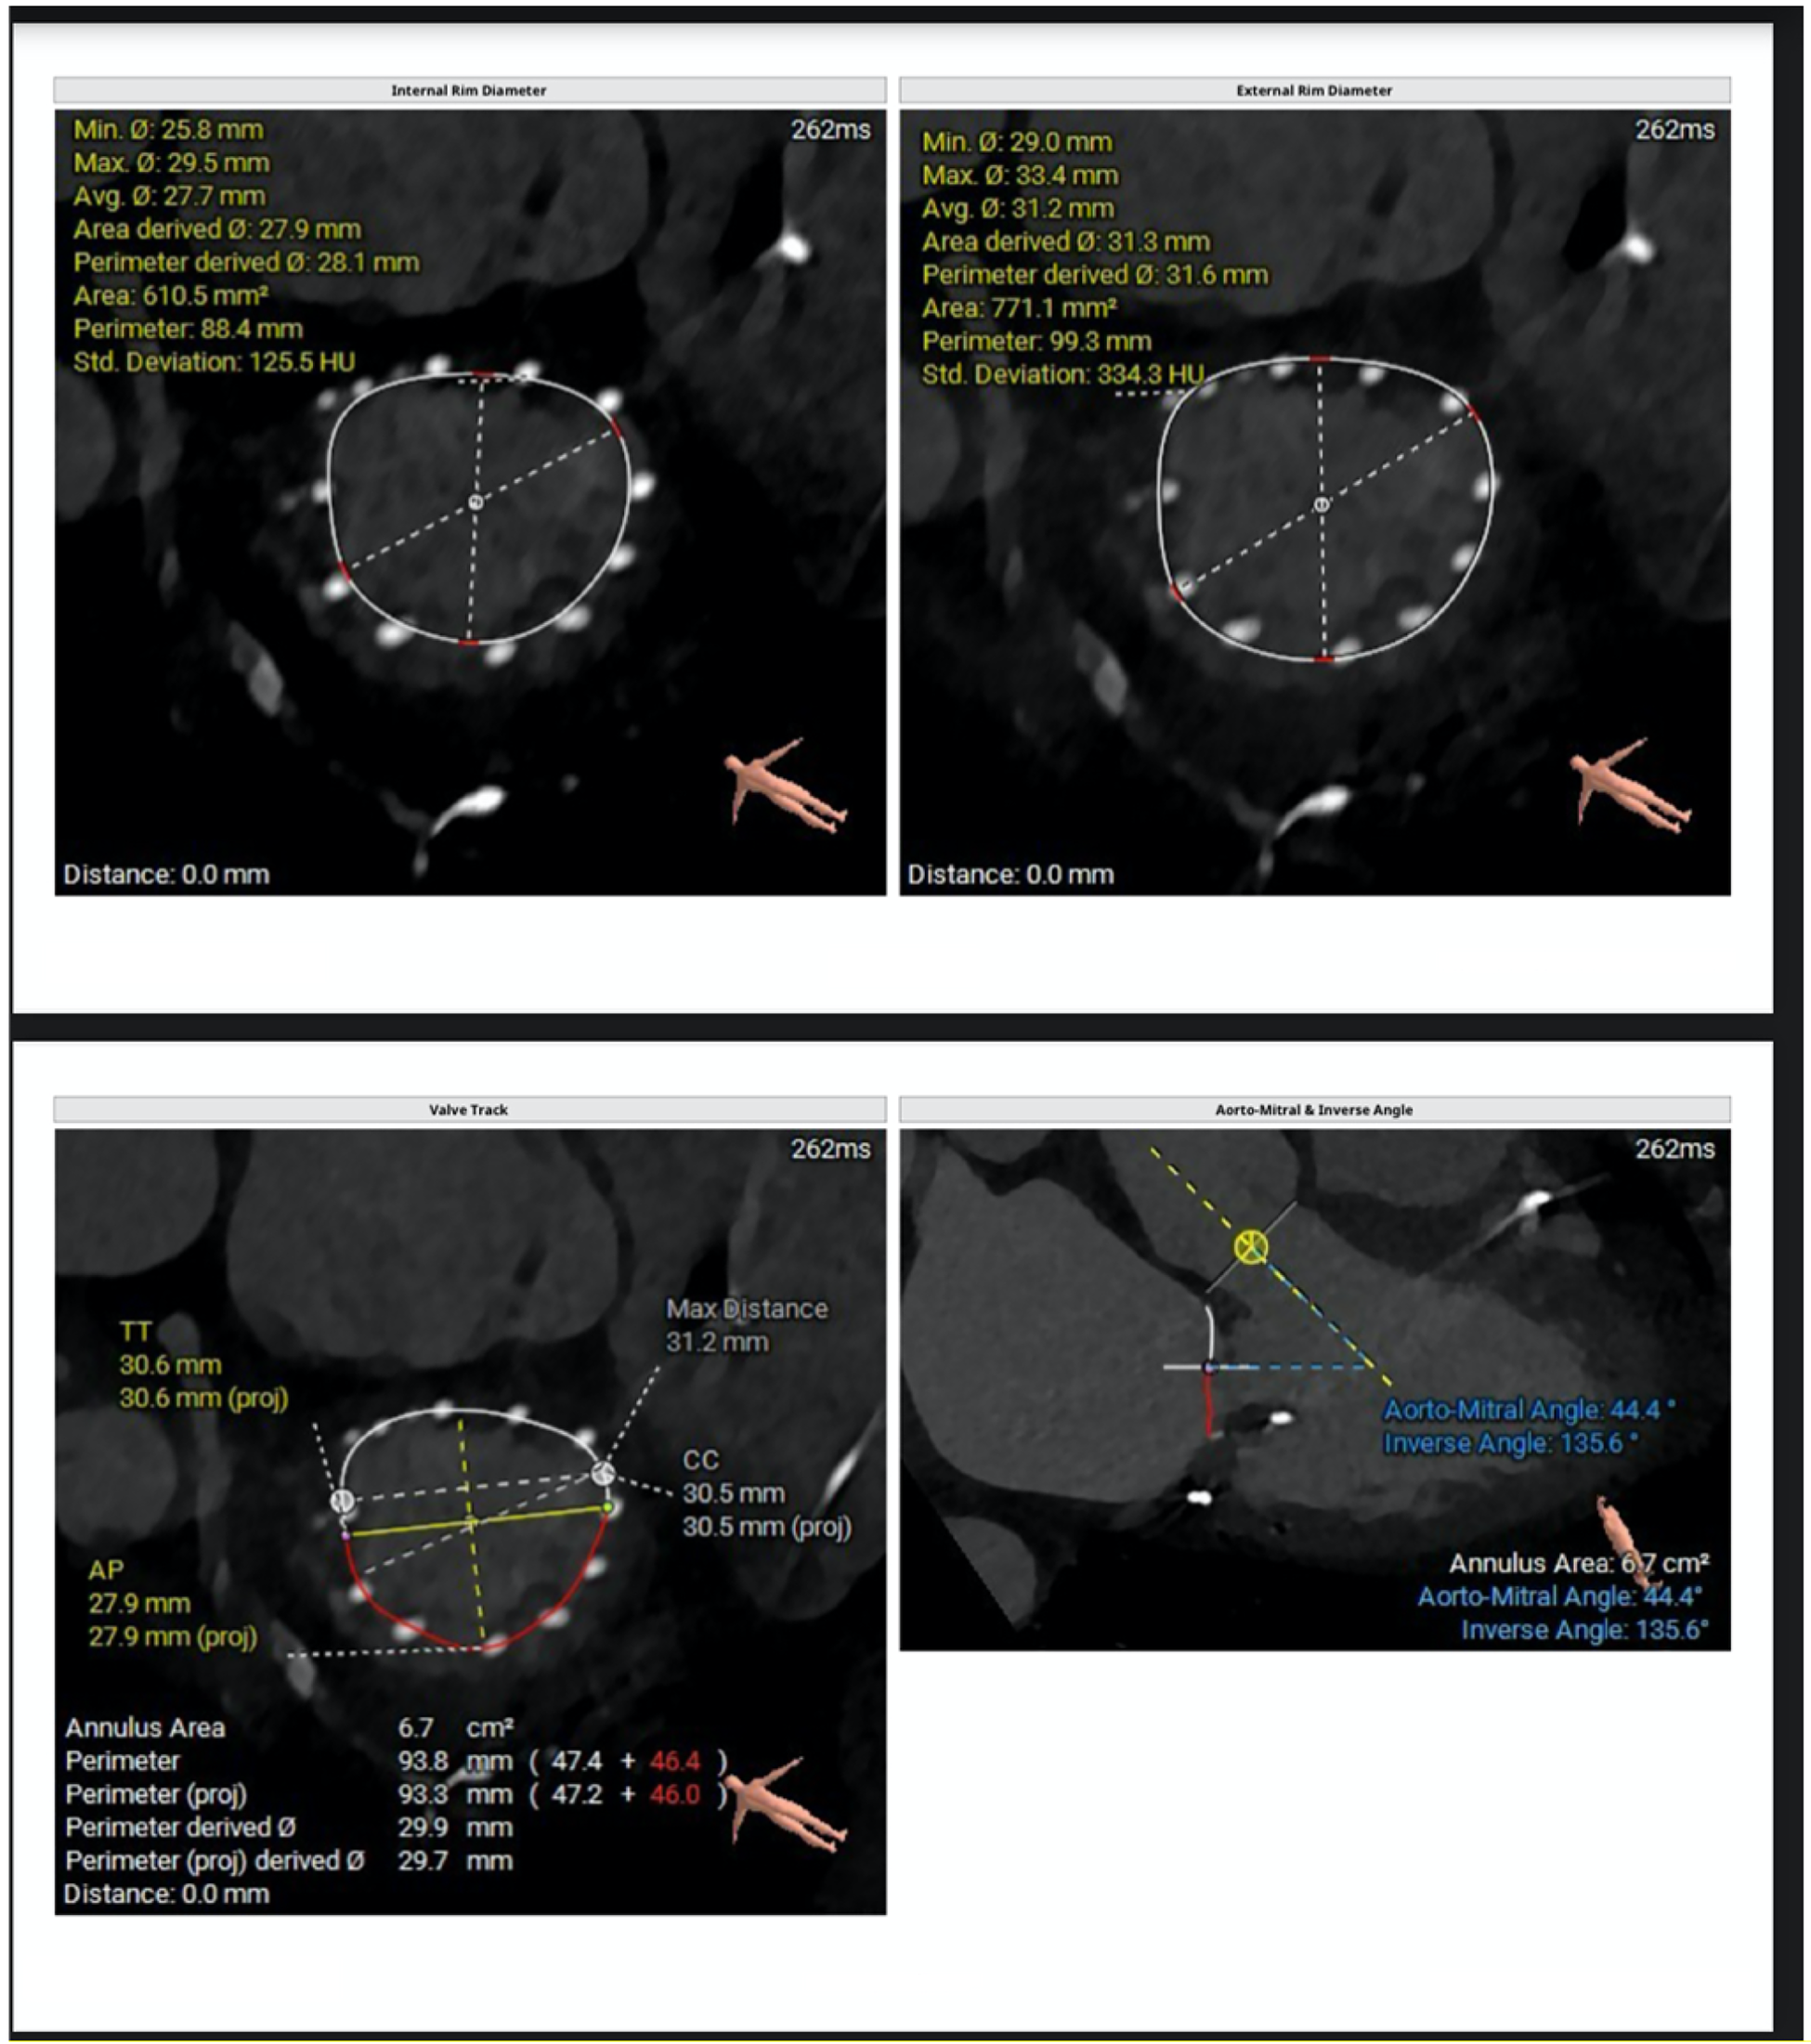

Figure 2

CT-derived measurements include mitral annular geometry with internal and external rim diameters, annular area and perimeter, and anteroposterior and commissure-to-commissure dimensions. The valve tracking analysis illustrates the spatial relationship between the mitral annulus and the left ventricular cavity. Additionally, the aorto-mitral angle and inverse angle are quantified to evaluate annular orientation and the potential impact on device alignment and left ventricular outflow tract interaction.